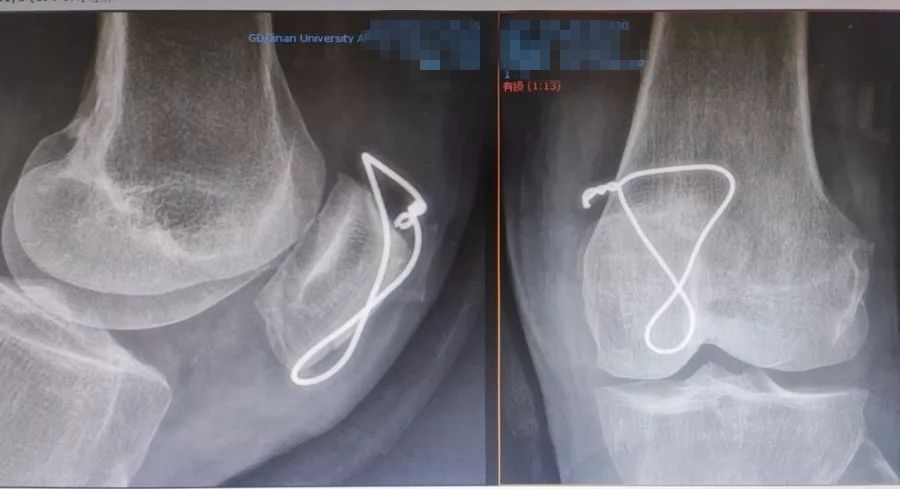

尽管现有克氏针、记忆合金髌骨爪等内固定方法,但暨南大学附属第一医院骨关节运动医学中心继承查振刚教授的环扎+"8"字张力带钢丝固定。这种内固定的方法, 操作简单,效果满意,适用于各种类型髌骨骨折,尤其是治疗髌骨粉碎性骨折更有其优越性。随着关节镜微创技术发展,科室的关节镜下经皮微创张力带钢丝内固定已有开展。

环扎+"8"字张力带钢丝固定

采用关节镜的辅助,可以监视髌骨关节面的软骨复位情况,探查关节内其他部位软骨、半月板、交叉韧带的情况并对关节内积血进行清理。关节镜监视下确认钢丝出入髌腱、股四头肌腱的软策划层面,监视下进行张力带钢丝的收紧,可更好地评估关节面软骨稳定及平整程度,更好地指导术后康复强度和进度。